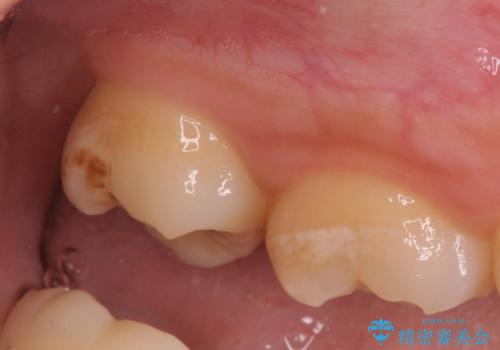

- 親知らず抜歯をご希望で来院されましたが、手前の歯が歯ぐきに覆われていたため抜歯と同時に歯ぐきの除去を行います。

歯の高さ十分がないと十分なブラッシングができなかったり、被せ物をする際に不利になってしまいます。

そのような時は周りの歯茎を除去することで歯の高さを出すことができる場合があります。

今回は親知らずの抜歯と同時に周りの歯茎の除去を行いました。